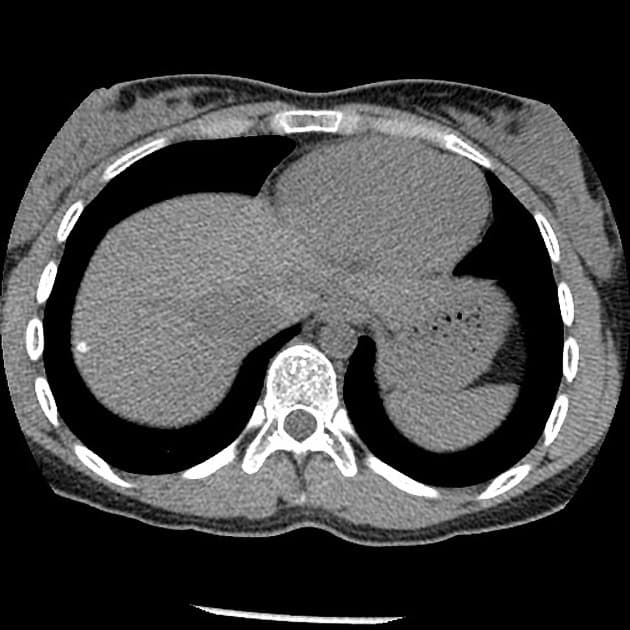

- Mô đệm tụy (pancreatic parenchyma) bị thay thế bởi nhiều nang tụy với số lượng vô số (innumerable pancreatic cysts).

- Các tổn thương nang không thông với ống tụy chính (main pancreatic duct).

Chụp cộng hưởng từ (MRI) và cộng hưởng từ mật tụy (MRCP) tụy ở bệnh nhân mắc bệnh Von Hippel-Lindau cho thấy các nang tụy vô số (innumerable pancreatic cysts).